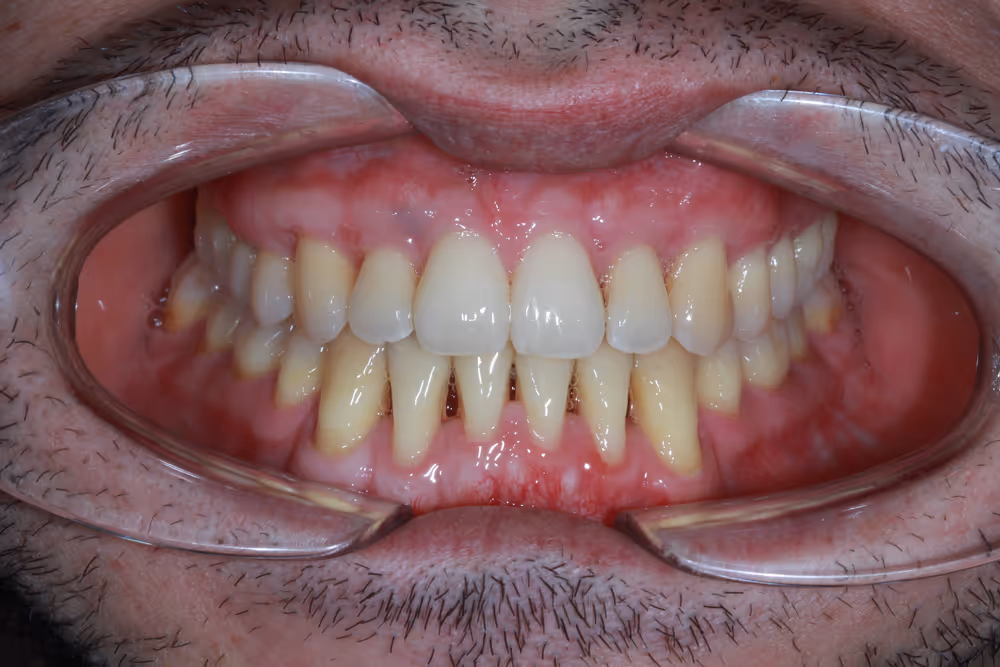

Te invitamos a conocer algunos de nuestros casos clínicos, donde podrás comprobar de primera mano la transformación que podemos lograr gracias a un enfoque multidisciplinar y a la excelencia que aplicamos en cada paciente.

En cada uno de estos casos, la especialización en las diferentes áreas de la odontología, el trabajo en equipo y la atención individualizada han sido claves para conseguir resultados óptimos.